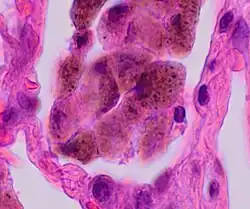

Comparison of pigmented pulmonary macrophages

| Disease | Macrophage name | Macrophage pigment appearance (HE stain) | Usual macrophage location | Associated medical history | Image | Image comment |

|---|---|---|---|---|---|---|

| Anthracosis | Black-brown granules | Interstitium (perivascular) |

|

Black arrow shows interstitial anthracotic pigment. Nearby macrophages (white arrow) can be presumed to contain anthracotic pigment. | ||